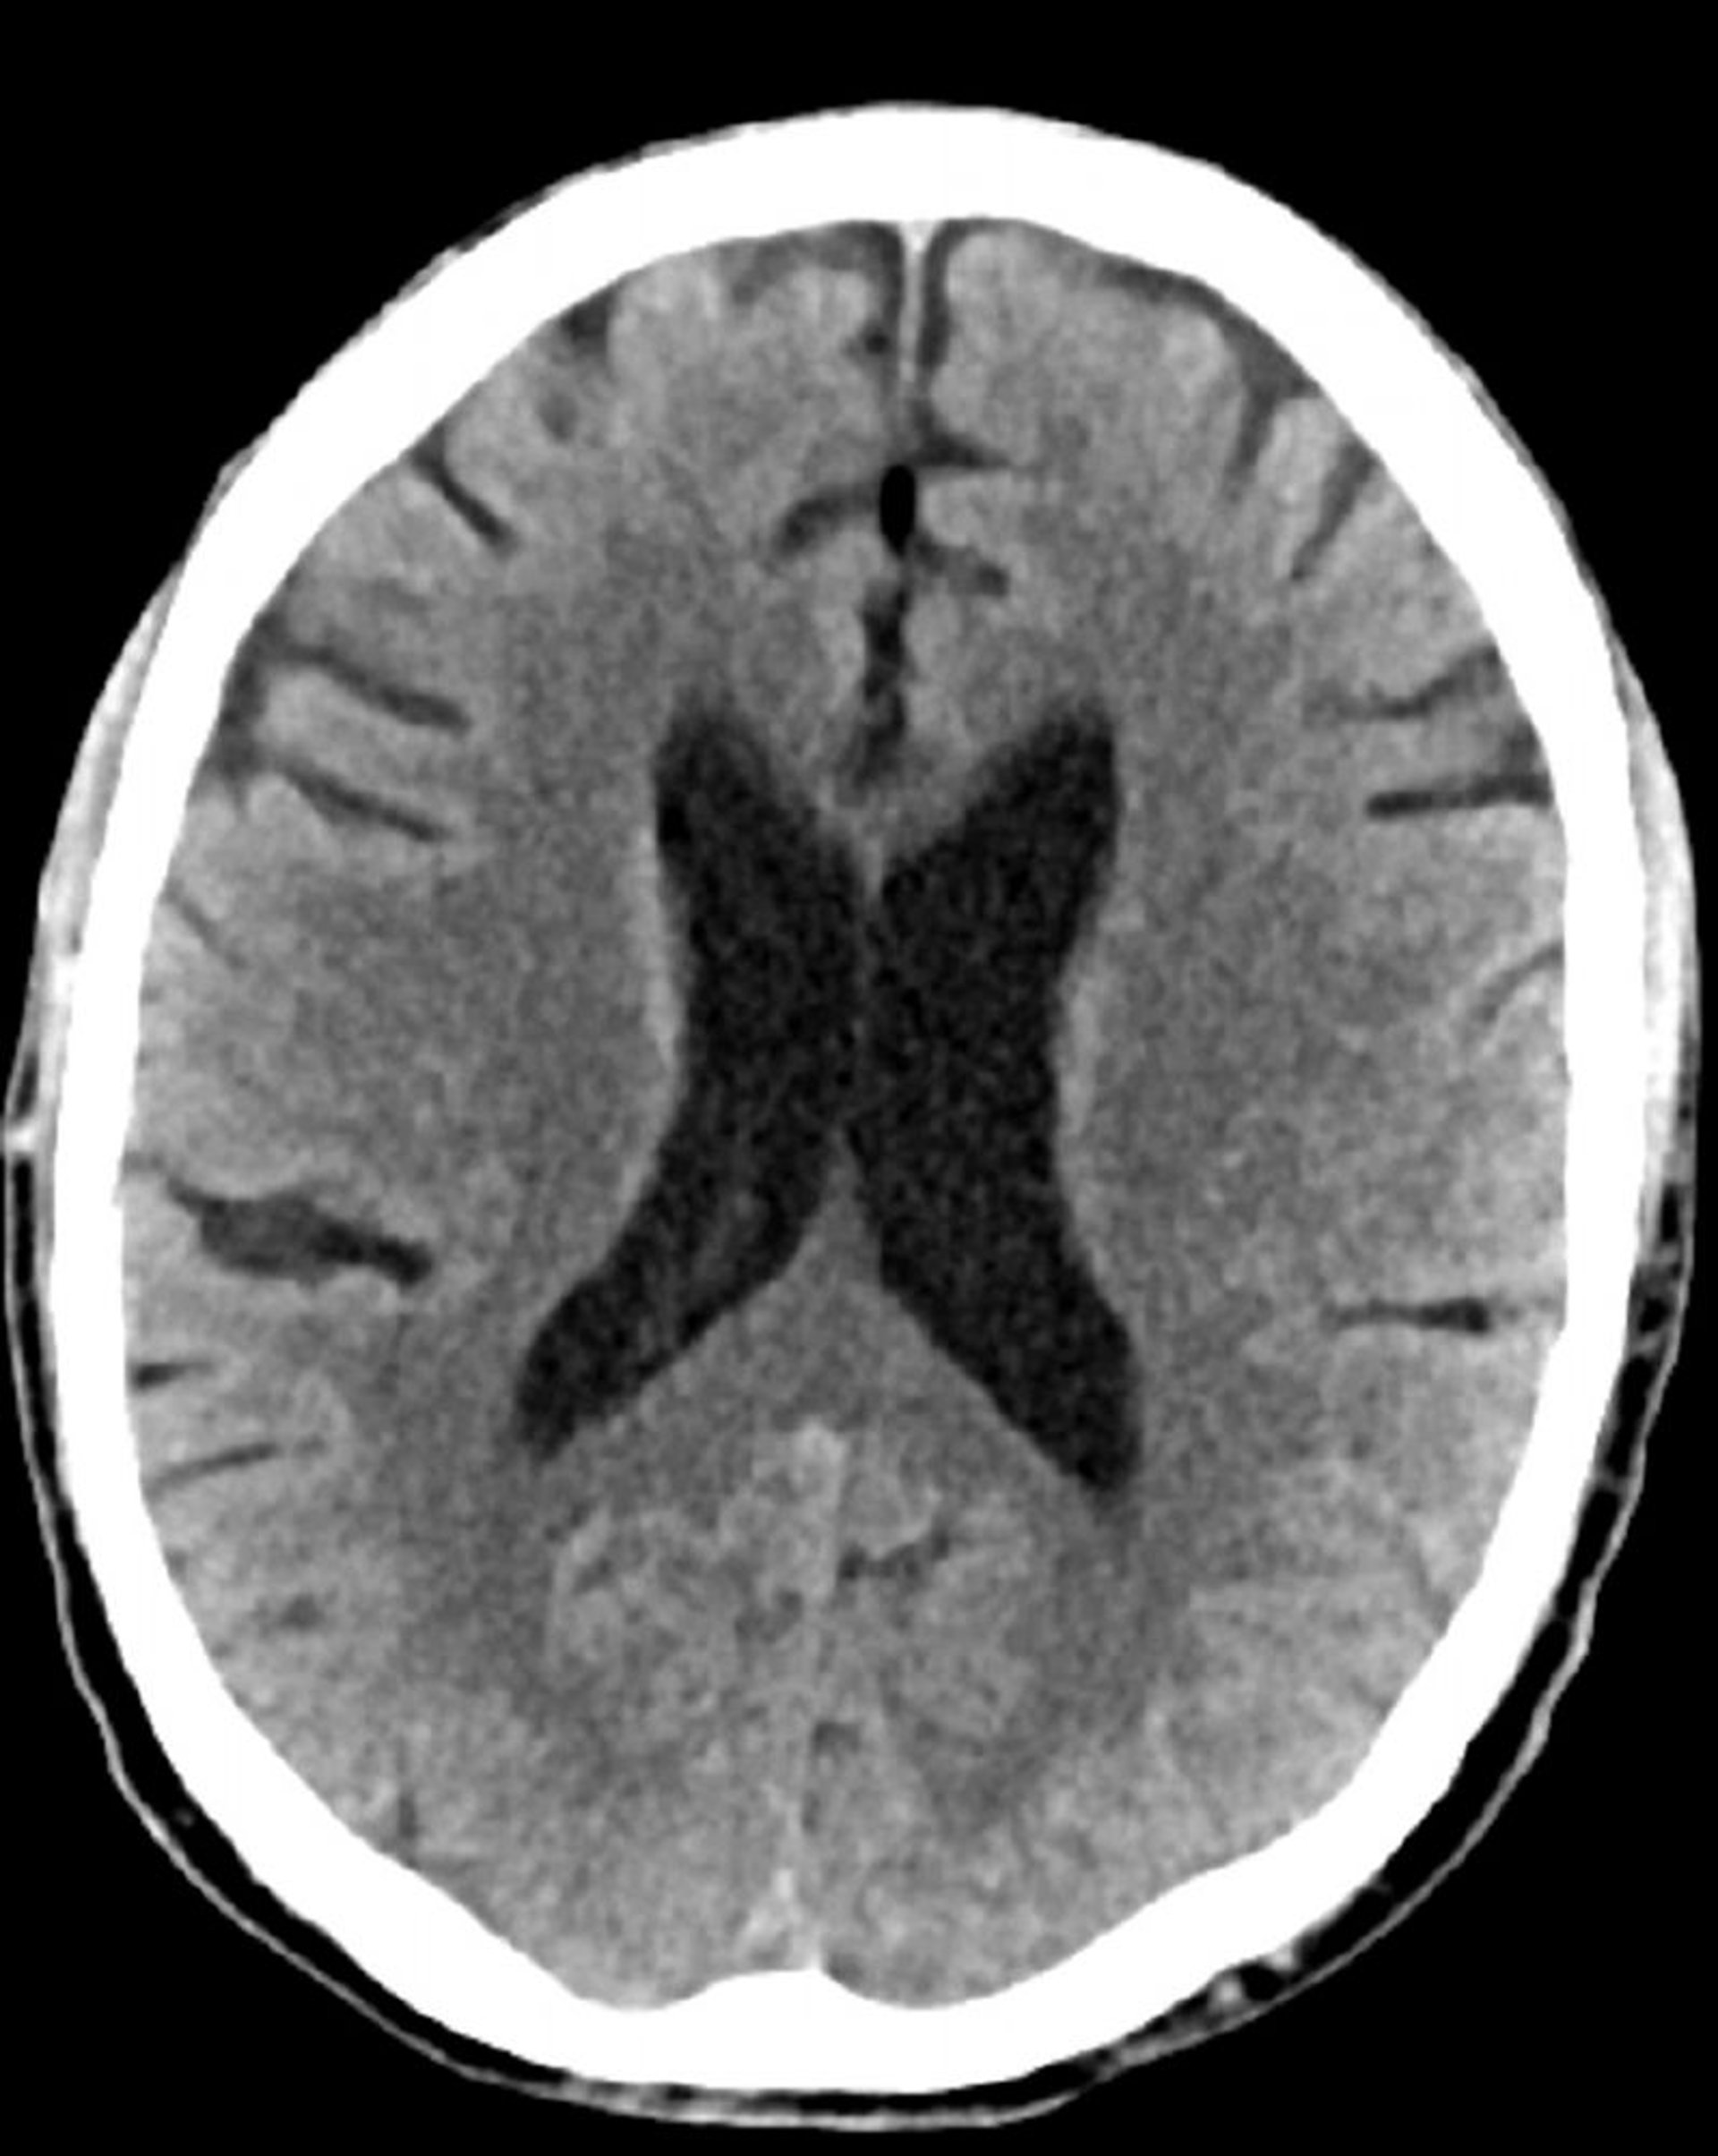

TC de crânio normal (adulto, idade 74) – – Diapositivo 4

Essa é uma TC normal da cabeça de um adulto com 74 anos. Quando comparada com a tomografia computadorizada normal da cabeça da pessoa de 30 anos de idade, os ventrículos e sulcos são maiores. Esses achados são normais nessa faixa etária.